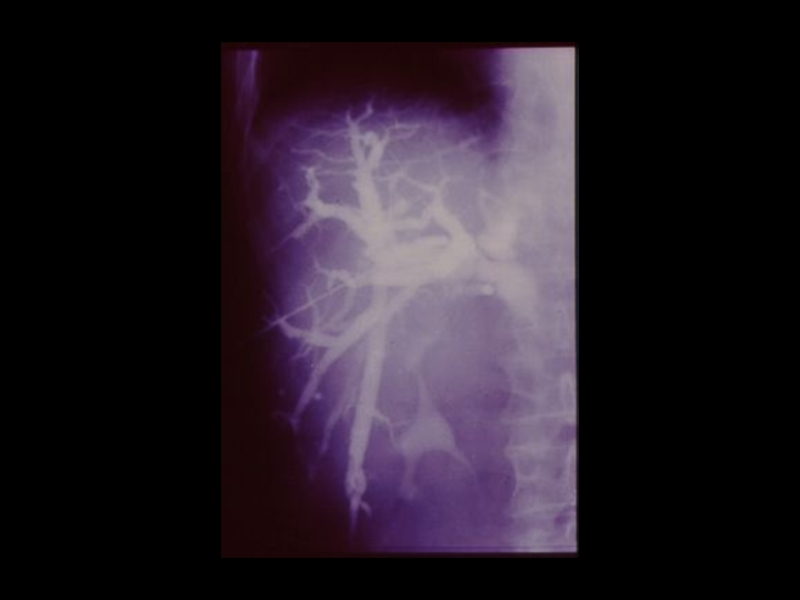

3. Специальные методы

(урография, бронхография, ангиография,

лимфография, пневмоартрография и другие)

Методы традиционной рентгенодиагностики:1. Общие методы   (рентгеноскопия, рентгенография)2. Частные методы   (флюорография, томография,

Слайд 39Йодсодержащие рентгеноконтрастные вещества:

I. Ионные - трийодзамещенные

1) Водные (

урографин, уротраст, верографин,

йодамид, триомбраст )

2) Масляные ( Йодолипол, майодил, лимфотраст)

II.Неионные ( 1974 )

1) Циклические трийодзамещенные неионные

мономеры ( Амнипак, омнипак, имагопак)

2) Неионные гексайодированные димеры

( молекула состоит из 2-х бензольных колец с

атомами йода)

- Везипак ( для ангиографии)

- Иотролан ( для миелографии )

Йодсодержащие рентгеноконтрастные вещества:I. Ионные - трийодзамещенные  1) Водные ( урографин, уротраст, верографин,